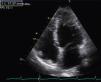

The transthoracic echocardiogram revealed apical LV hypertrophy with a typical spade-like geometry of the LV cavity at end-diastole (LV wall thickness 17 mm) (Figure 2) and LV diastolic dysfunction (impaired relaxation) (Figure 3) with normal ejection fraction. No structural or functional valve disease was present.